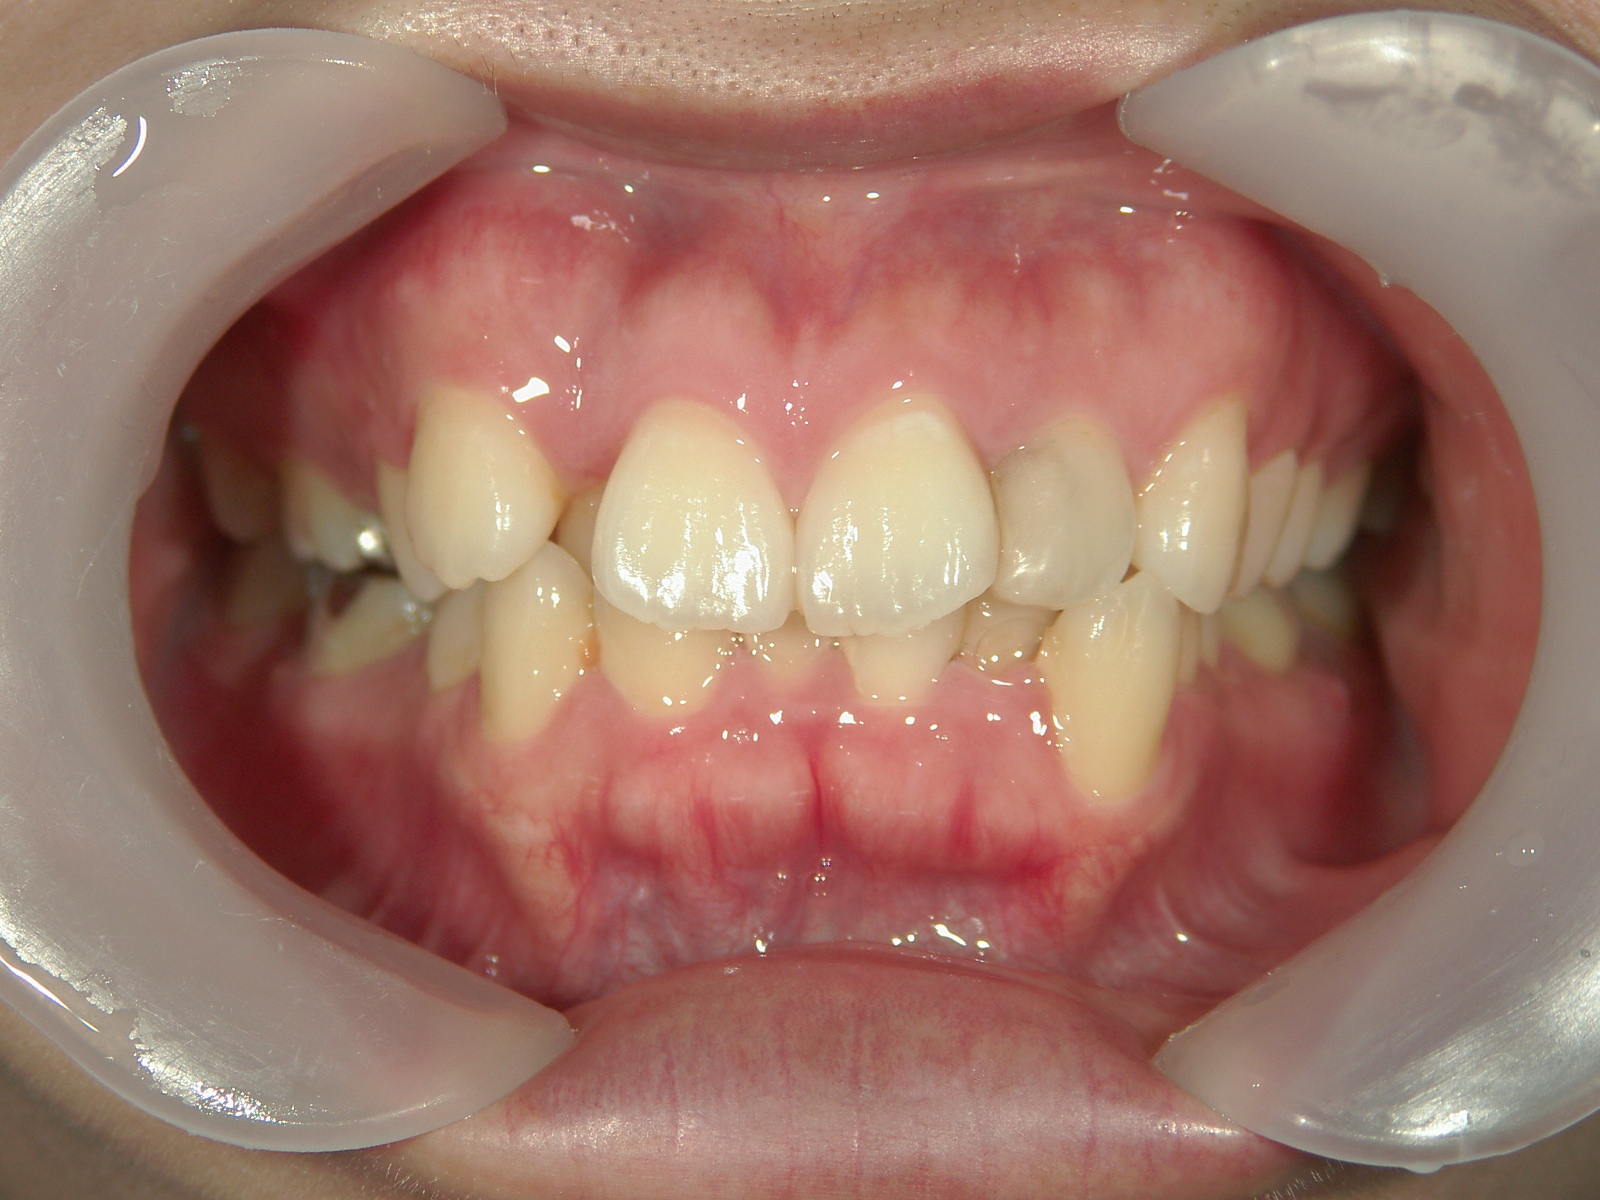

舌側ワイヤー矯正 症例(25)

主訴: 歯並びが気になる

カテゴリー : ガタガタ(叢生)